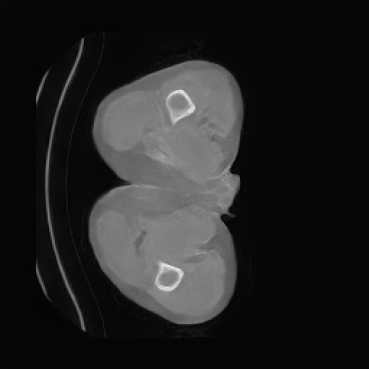

Appendix D More Generated Images Slices

![[Uncaptioned image]](x2.png)